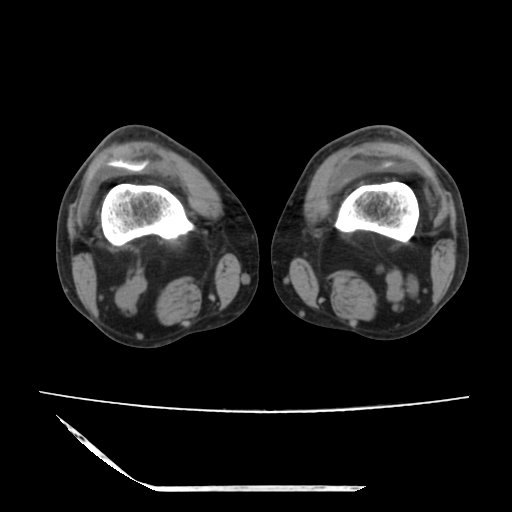

标题: CT13225:老年男性,左膝关节疼痛数月;请各位老师讨论。 [打印本页]

标题: CT13225:老年男性,左膝关节疼痛数月;请各位老师讨论。

骨质增生,骨性关节面硬化,关节积液,考虑退行性骨关节病

关节腔内少量积液,关节面退变。

双膝退变

骨质增生,骨性关节面硬化,关节间隙失常,关节积液,考虑退行性骨关节病.

骨质增生,骨性关节面硬化,关节积液,考虑退行性骨关节病。

这个病例诊断:退行性骨关节炎